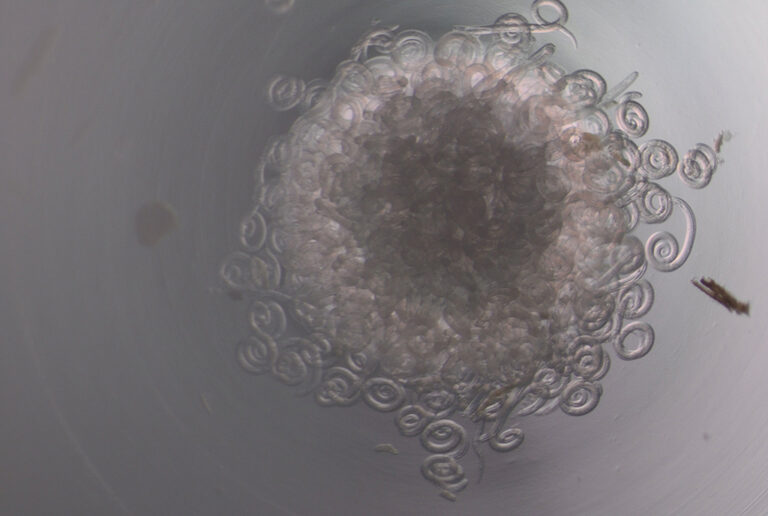

Keeritsussid on mikroskoopilised ümarussid, mis põhjustavad inimesel keeritsusstõbe ehk trihhinelloosi. Inimene nakatub parasiidi vastseid sisaldava liha või piisava kuumtöötluseta lihatoodete söömisel. Nakkusallikaks Eestis on sagedamini metssiga, harvem karu. Seetõttu on oluline, et liha oleks enne toidulauale jõudmist eelnevalt nõuetekohaselt kontrollitud.